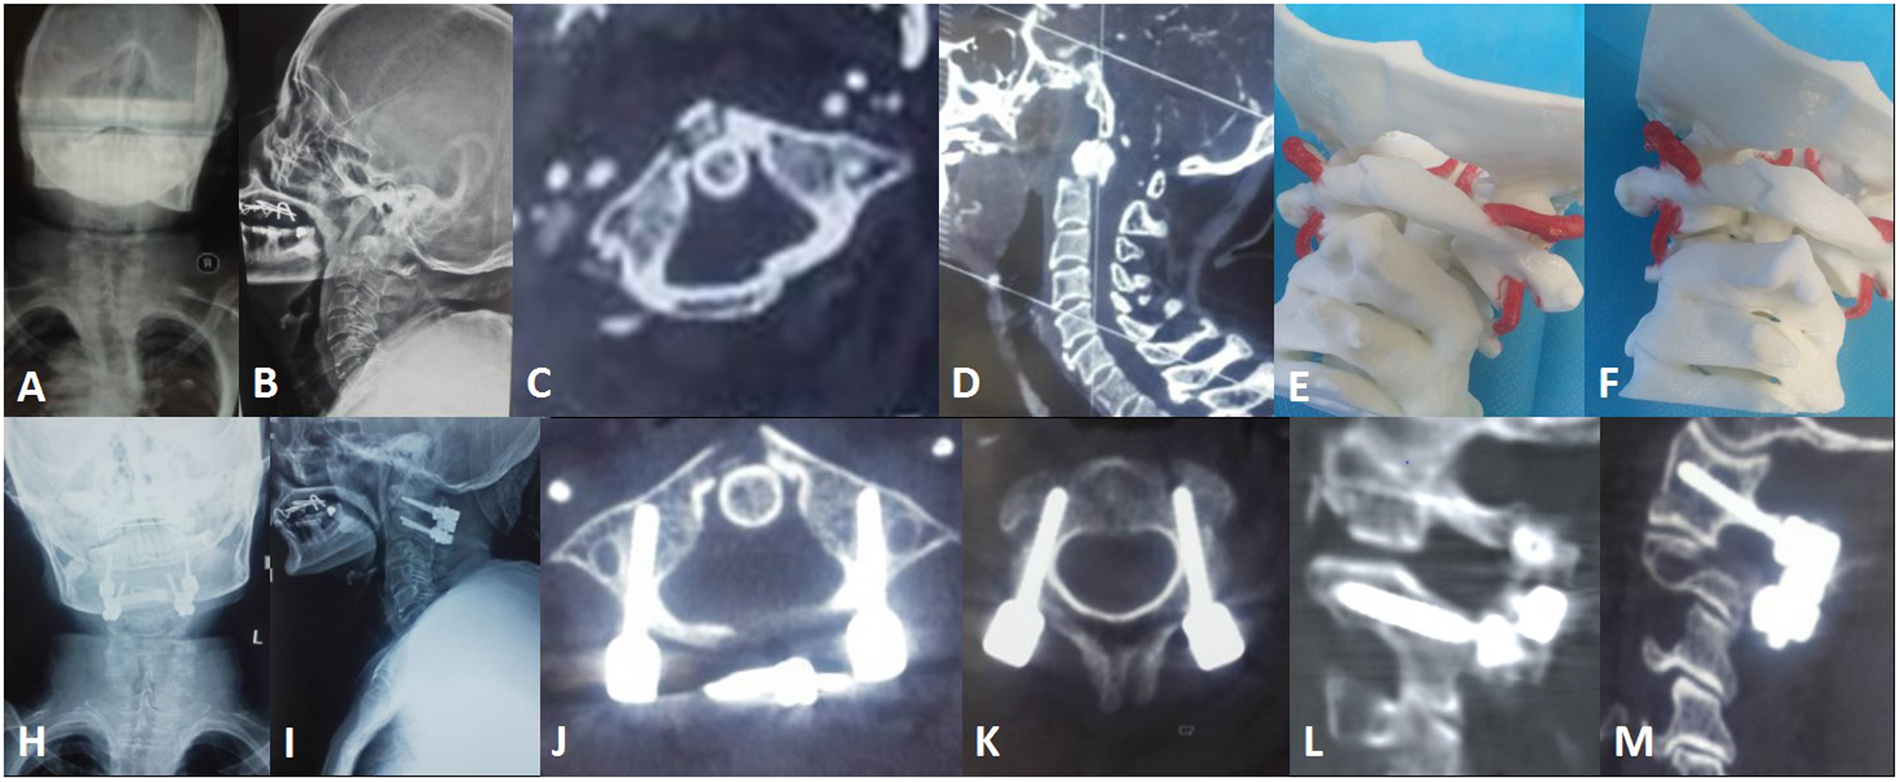

Figure 5

A 55 year-old female with atlantoaxial dislocation underwent posterior reduction and C1 pedicle-C2 pedicle internal fixation assisted by a 3D-printed life-size model. (A–D) Preoperative X-ray photographs showing a Jefferson fracture and odontoid fracture. (E) 3D life-size model showing that the vertebral artery on the left side was closer to the middle line and revealing the best screw trajectory. (I–M) Postoperative photographs showing that the screw position was satisfactory.